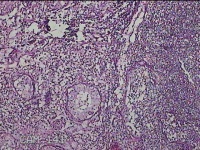

左侧腋下结节

性别

女

年龄

46岁

临床诊断

皮下结节

一般病史

发现左侧腋下一结节1周,伴局部隐痛不适,无发热。

标本名称

大体所见

灰白暗红色组织1.8x1.3x0.3cm一块,表面带梭形皮肤1.8x0.5cm,皮下见结节1.2x0.8cm,切开结节呈实性,切面灰白淡黄色,质软。

炎症性病变。